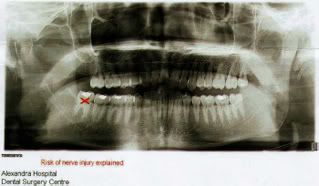

because of this